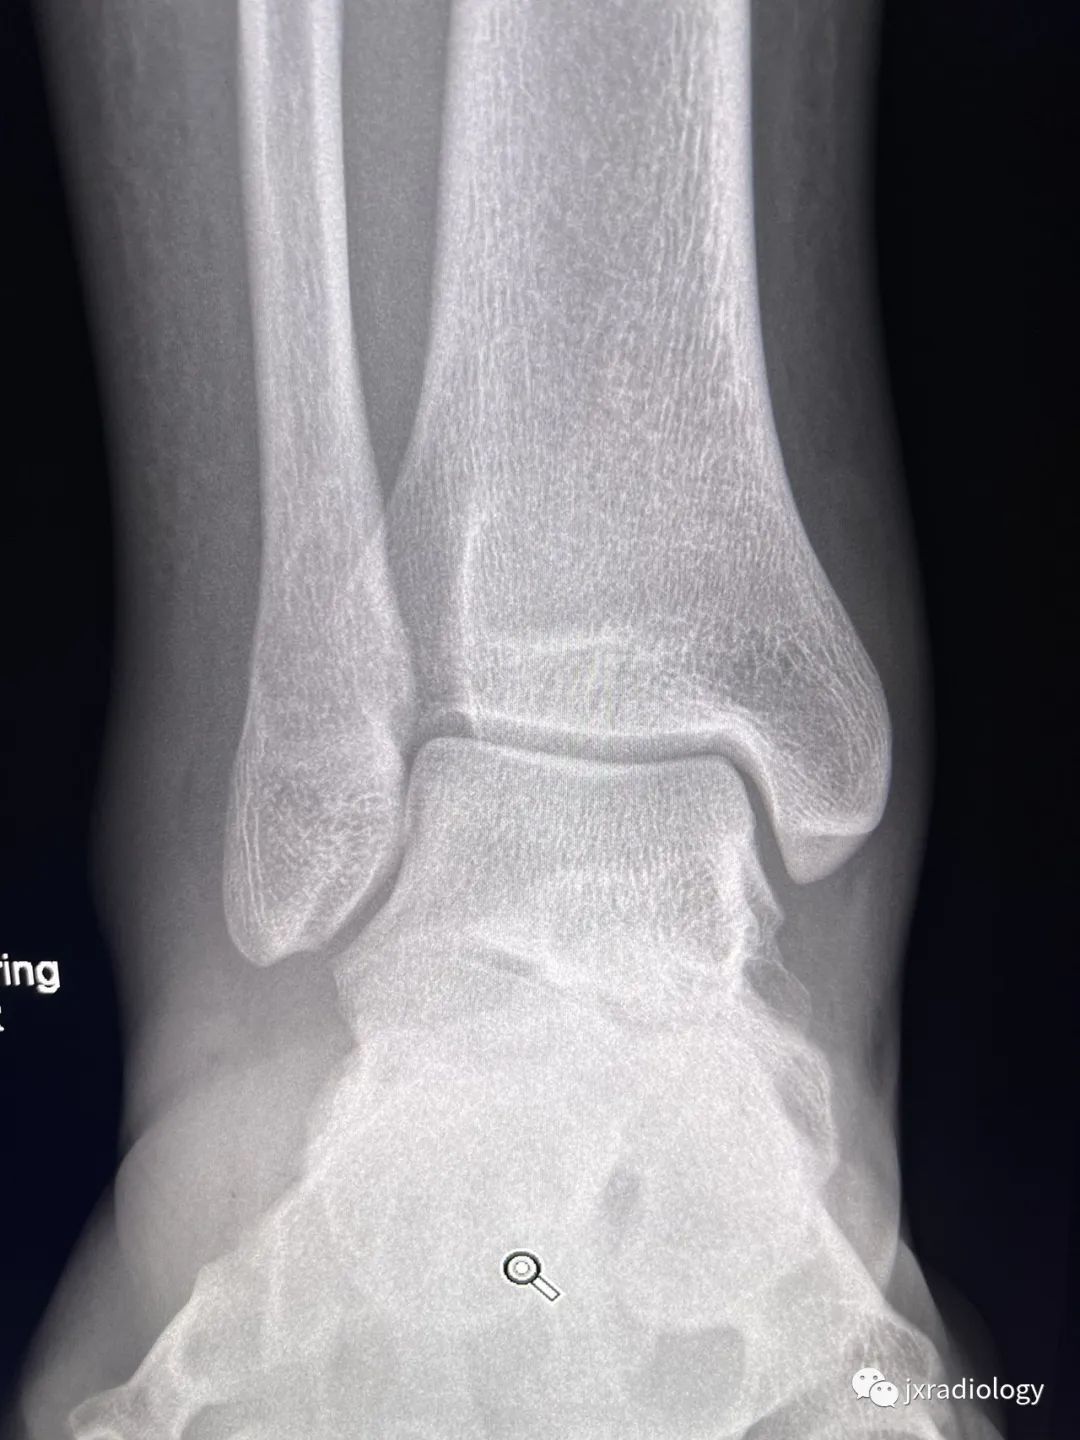

男,33岁,外伤后踝关节正侧位X线片,能发现哪些异常?

1. Distal fibular fracture2. Distal tibiofibular syndesmotic ligament disruption 3. Simple bone cyst (SBC) calcaneum1、腓骨远端骨折2、下胫腓联合损伤;3、跟骨囊肿